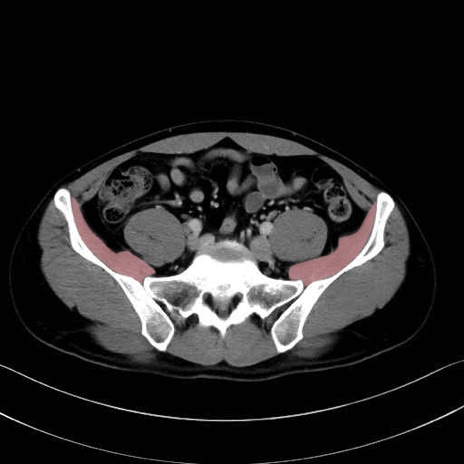

2. 腸腰筋群と骨盤底筋

腸骨筋 (Iliacus)